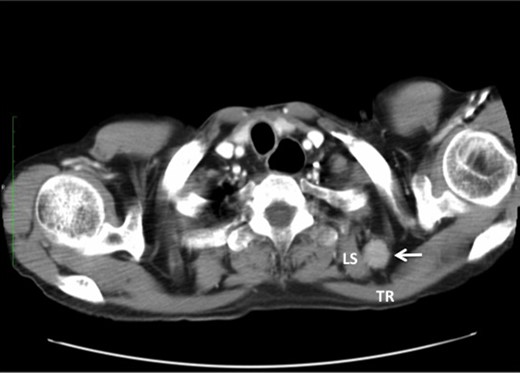

We have had three cases of this unusual LNM from cancer of the thoracic esophagus to date. Clinicopathological characteristics and survival are presented in Table 1. This unusual LNM developed after esophagectomy in two patients (cases 1 and 2, Fig. 2) and was found at presentation in a third patient (case 3, Fig. 3).

Undifferentiated carcinoma was confirmed by excisional biopsy of the tumor located between TR and LS (arrow).